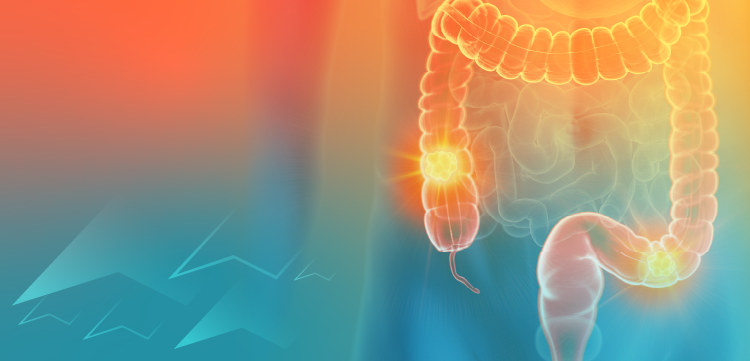

The initial physical examination showed the following: heart rate, 100 beats per minute; blood pressure, 108/65 mm Hg; oxygen saturation, 94% on room air (measured by pulse oximetry); and normal temperature. Chest auscultation revealed diminished breath sounds over the right hemithorax and bilateral expiratory wheeze. The patient's chest radiograph showed a right lower lobe infiltrate. A CT scan of the chest showed a right sided endobronchial mass and right lower lobe atelectasis (

A mediastinoscopy was done, and the lymph nodes sampled were negative for malignancy. A positron emission tomography scan was negative for primary malignancy elsewhere in the body. The patient's pneumonia worsened, and postobstructive necrotizing pneumonia developed despite treatment with broad-spectrum antibiotics.

A right pneumonectomy with mediastinal lymph node resection was done. The pneumonectomy specimen demonstrated a 6.5 × 4.5 × 4-cm mass surrounding the bronchus intermedius and extending to the right lower lobe. The tumor was diagnosed as an infiltrating synovial sarcoma involving the diaphragm and mediastinum, but the mediastinal lymph nodes and surgical margins were free of the tumor.

Pulmonary sarcomas are divided into 4 categories: leiomyosarcomas, fibrosarcomas, hemangiopericytomas, and synovial sarcomas. Pulmonary sarcomas are usually parenchymal and metastatic in origin. Primary pulmonary synovial sarcoma is an extremely rare tumor that may arise from the lung parenchyma, bronchial tree, or pulmonary artery. This type of sarcoma was underdiagnosed before the use of immunohistochemistry and electron microscopy.

This tumor usually presents as a lung parenchymal mass. In the largest case series on thoracic sarcomas, most tumors presented as mediastinal, pulmonary, or pleural masses. Published cases of pulmonary parenchymal synovial sarcoma showed the tumor size to be between 2 and 16 cm.1-9

Patients with endobronchial lesions theoretically have a better prognosis because of early symptoms and presentation.8 Most pulmonary parenchymal sarcomas reported in the literature were treated with surgical resection. Lobectomy or pneumonectomy was done depending on the size of the tumor and the extent of involvement. Chemotherapy and/or radiotherapy was given postoperatively in few cases.1 The tumor is poorly responsive to chemotherapy, and recurrence is common.